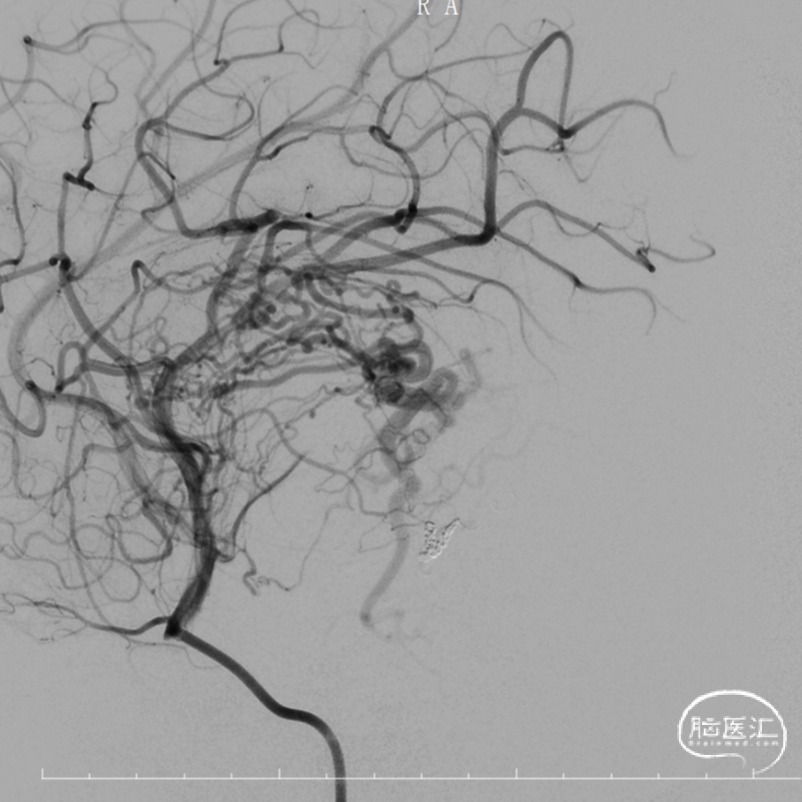

DSA

经脑血管造影及MRI可见肿瘤血供丰富,可见左侧大脑中、脉络膜前、大脑后动脉多根血管分支供血,考虑患儿年龄情况,最终拟定行左颞叶占位性病变介入栓塞术+开颅探查左颞叶占位性病变切除术。